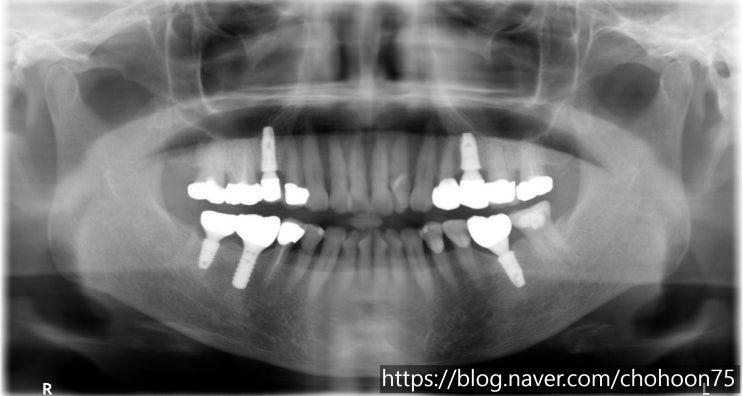

[조훈치과] 타치과에서 식립한 임플란트 재수술 치료 증례

안녕하세요. 조훈 치과입니다. 임플란트는 자연치아와 가장 유사한 기능과 심미성을 갖추고 있어 최근 많이...